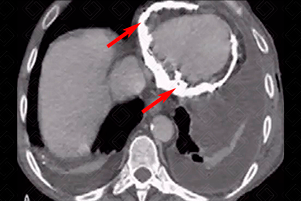

Texto alternativo para a imagem Figura 2. Créditos: Dra. Elazir Mota - Rio de Janeiro/RJ

Descrição da figura 2: Tomografia computadorizada do tórax evidenciando calcificação grosseira ao redor do pericárdio (setas vermelhas). A causa, nesse caso, foi tuberculose. Observe, ainda, que paciente apresentava derrame pleural bilateral.

Exames de imagem: A calcificação pericárdica pode ser visualizada tanto na radiografia (figura 1) quanto na tomografia computadorizada do tórax (figura 2).

• Tomografia computadorizada do tórax: Imagem espontaneamente densa no estudo tomográfica, densidade bastante elevada.